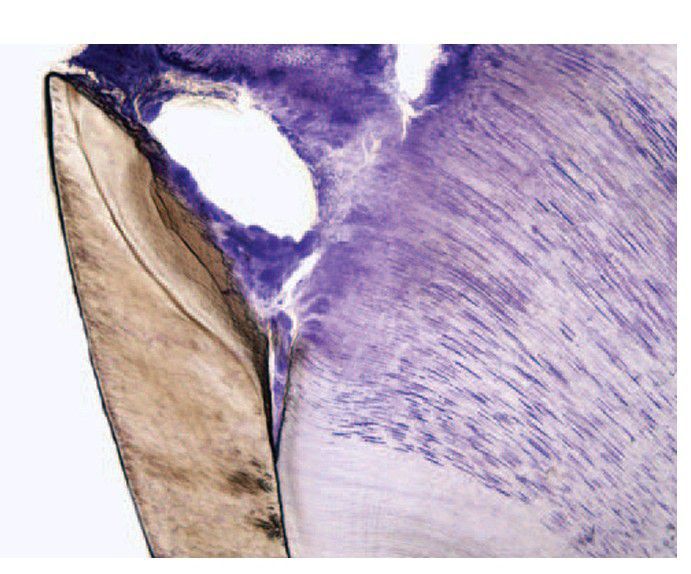

Low-power view of caries spreading along the amelodentinal junction. Note how it spreads only a small distance in advance of caries in dentine. The amelodentinal junction is only a little more susceptible to carious spread than dentine.